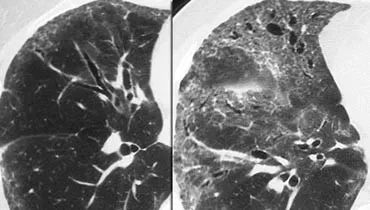

下图HP,GGO呈马赛克分布。

一些小叶受累,而另一些则没有。

鉴别诊断为过敏性肺炎、毛细支气管炎或血栓栓塞病。

过敏性肺炎通常表现为磨玻璃密度的小叶中心结节(腺泡结节)。

当它们汇合时,HRCT显示弥散的GGO。

过敏性肺炎(HP)是一种由吸入各种有机粉尘中所含抗原引起的过敏性肺病。

HP通常以两种形式出现,一种是镶嵌分布的GGO,如本例;另一种是磨玻璃密度的小叶中心结节(腺泡结节)。

下图患者,GGO呈马赛克分布。

这里的线索是GGO区域肺动脉(箭头)的增大。

GGO的出现是由于慢性血栓栓塞性疾病导致少血肺旁的高灌注所致。

下图,另一位病人的GGO呈马赛克分布。

再一次,GGO的出现是由于慢性血栓栓塞病造成的肺过度灌注。

附壁栓子和血管内间隔是部分再通的慢性血栓栓子的典型表现。